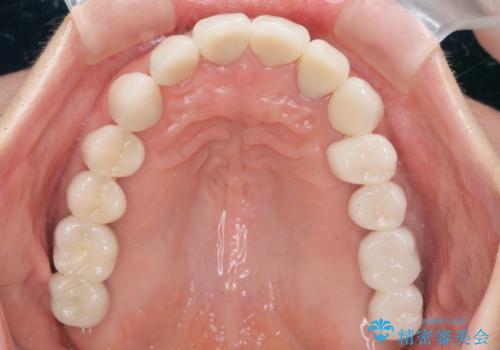

不適合やすり減ったクラウンを全て除去し、虫歯を丁寧に除去したのち精密なセラミック治療を行いました。

しっかりと調整された咬合関係と、見た目の改善に大変喜んでいただくことができました。